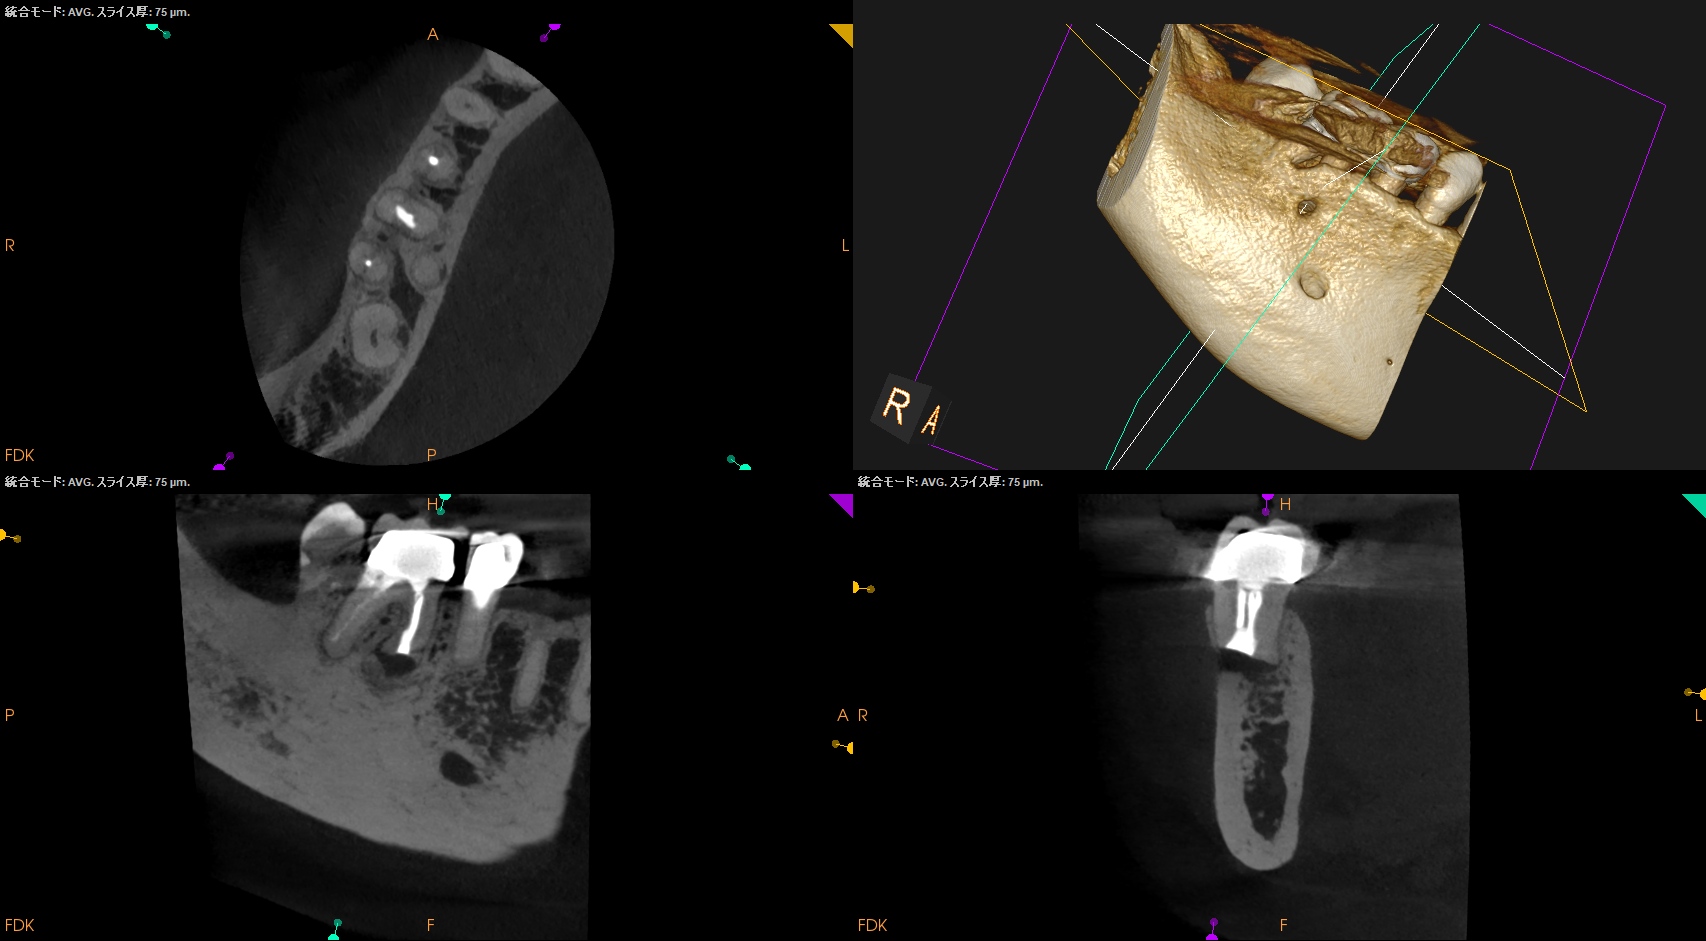

#30 M Apicoectomy 8M recall(2026.2.6)

骨欠損は完治していないが、検査で臨床症状が消失した点と、

術直後が、

骨欠損が今よりも大きく8ヶ月で縮小していることから問題はないと考える。

術直後と比較した。

完治ではないが大幅に問題が解決していることがわかる。